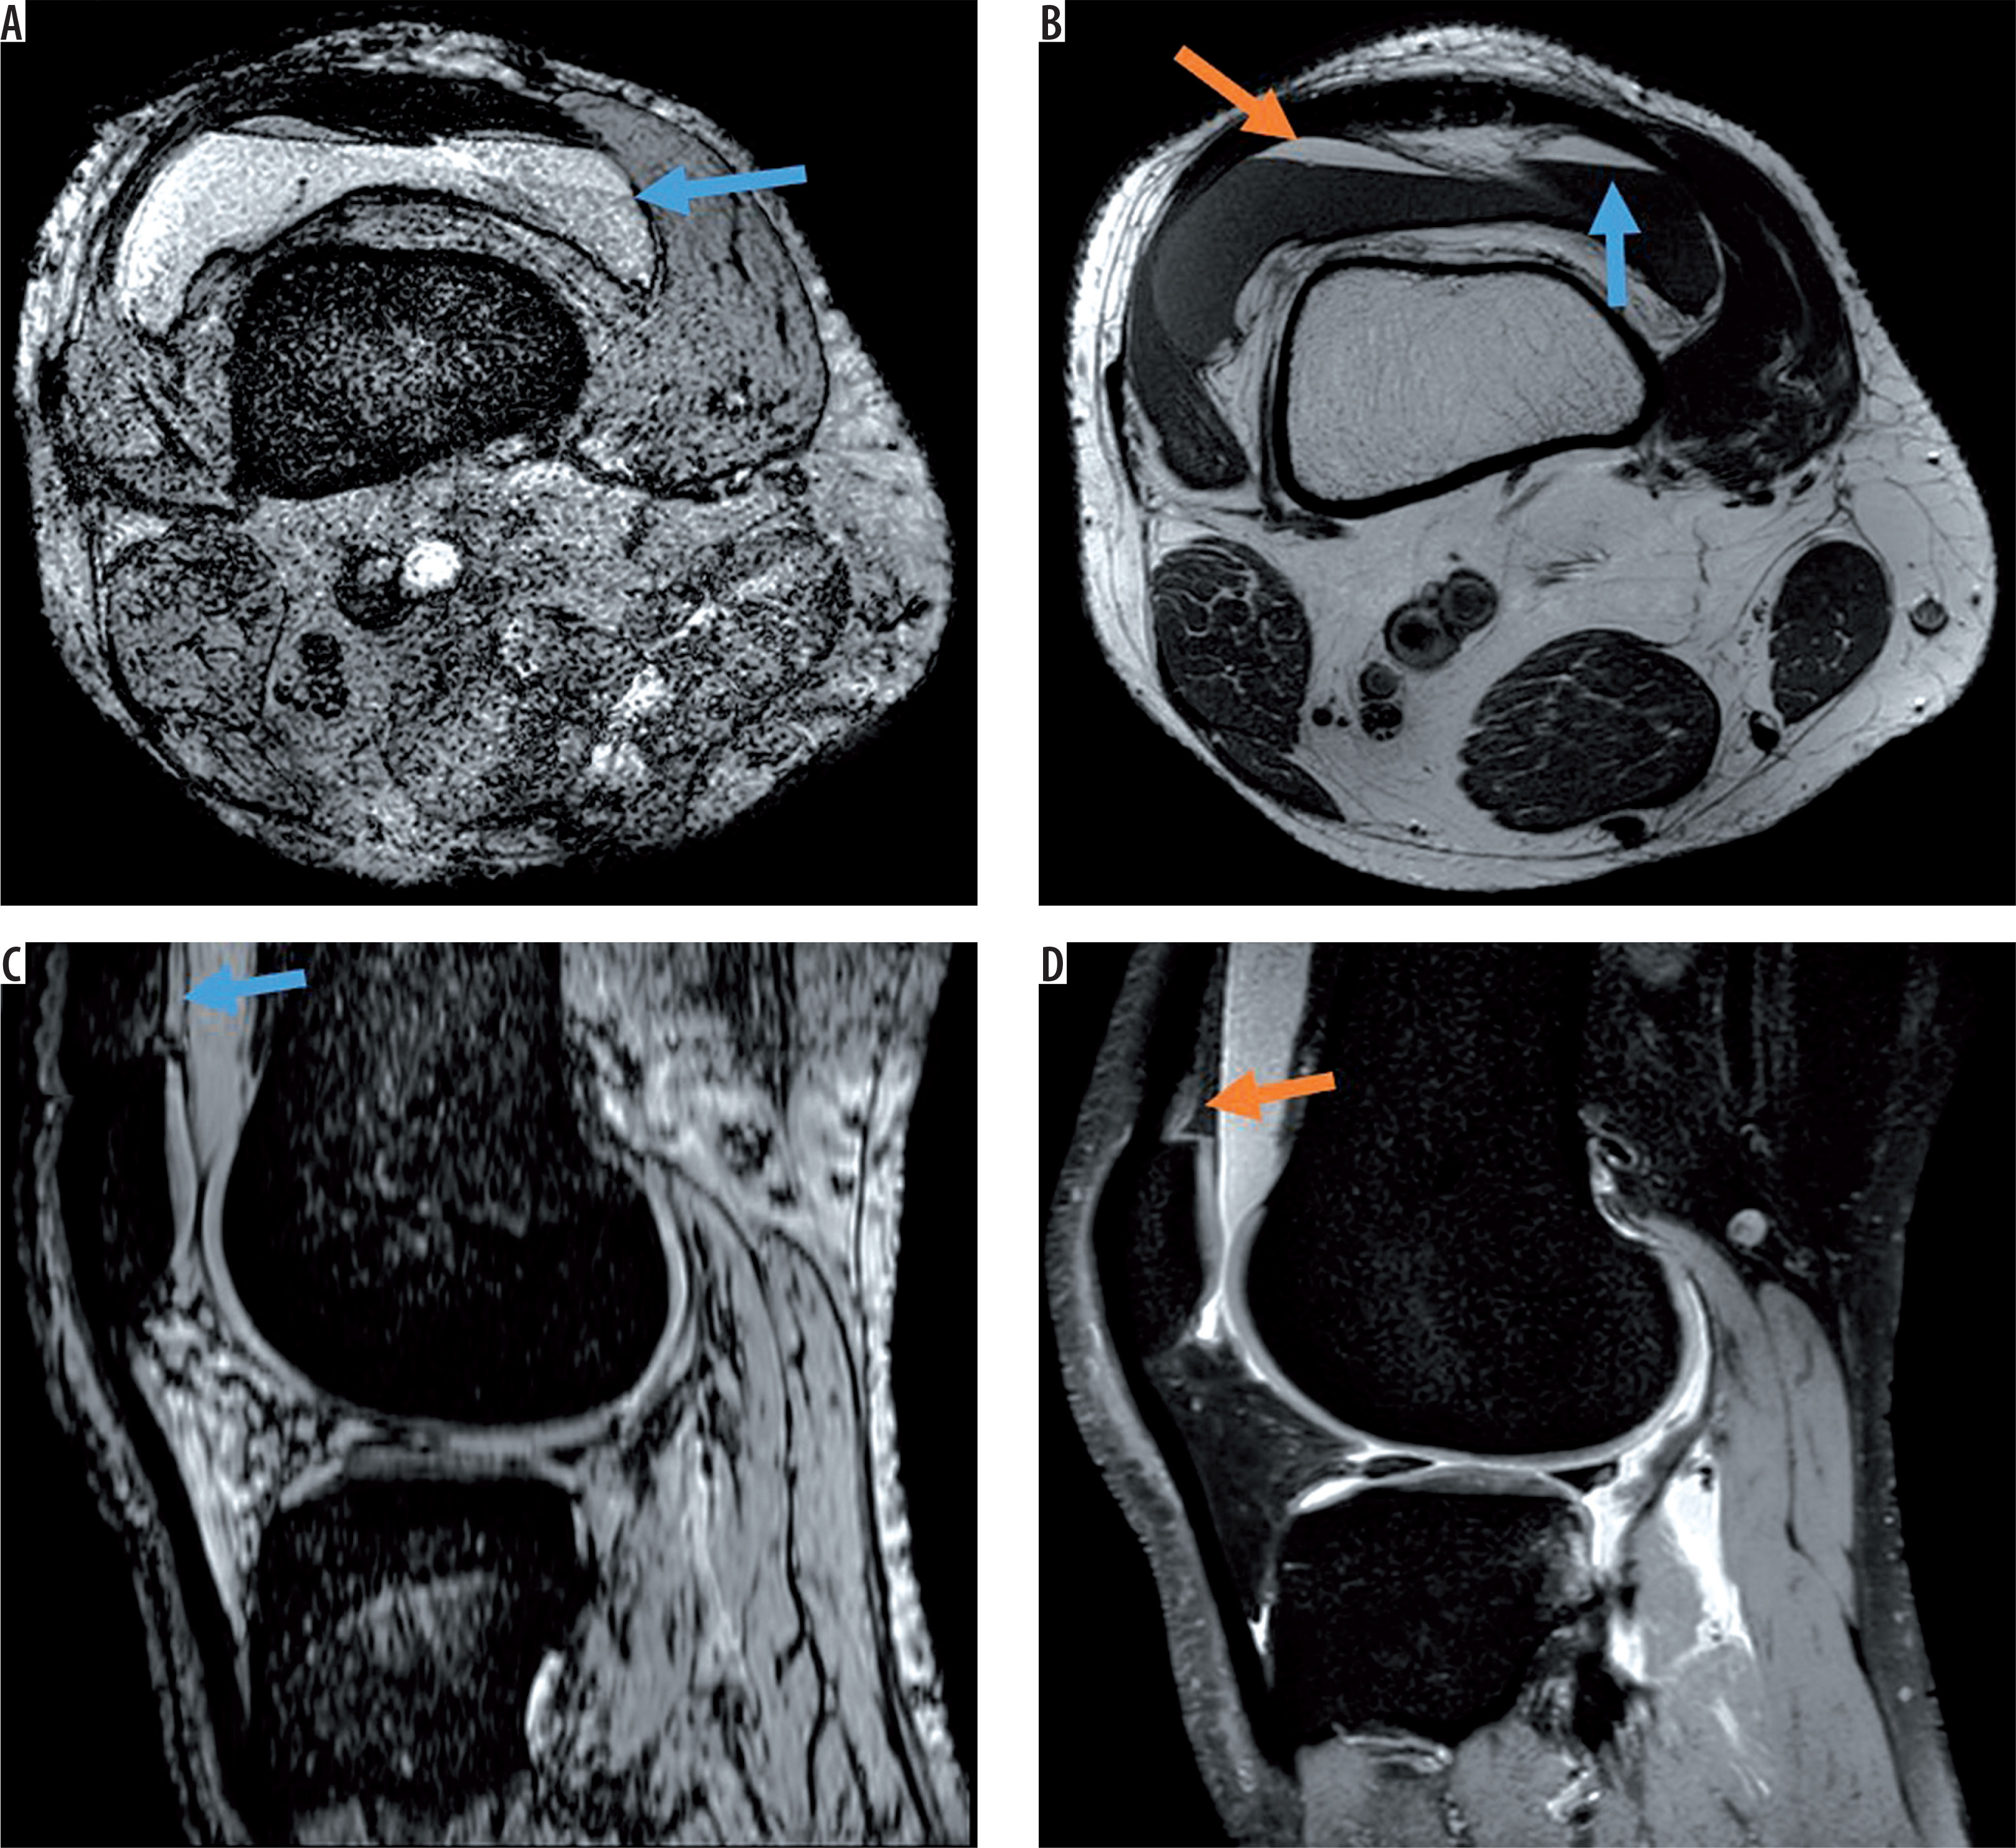

Figure 2

Post-traumatic case with intra- and periarticular haemorrhage. On A) axial susceptibility-weighted imaging (SWI) sequence and C) sagittal SWI excellent visibility of the periarticular haemorrhage with bold hypointensity in the anterior capsule (blue arrow) and intra-articular blood components (hypointense dots, orange arrow), B) corresponding axial proton density (PD)-weighted, and D) sagittal PD-weighted imaging without post-traumatic periarticular blood components. Postoperative changes (red arrows)

Post-traumatic haemorrhage displaying blood on all sequences. A) Axial susceptibility-weighted imaging (SWI) and C) sagittal SWI display intraarticular blood level with typical fat/fluid level (blue arrow) also visible on the B) axial T1-weighted image (hyperintense fat layer on top of fluid [orange arrow]) and corresponding hypointensity on the D) sagittal proton density-weighted image